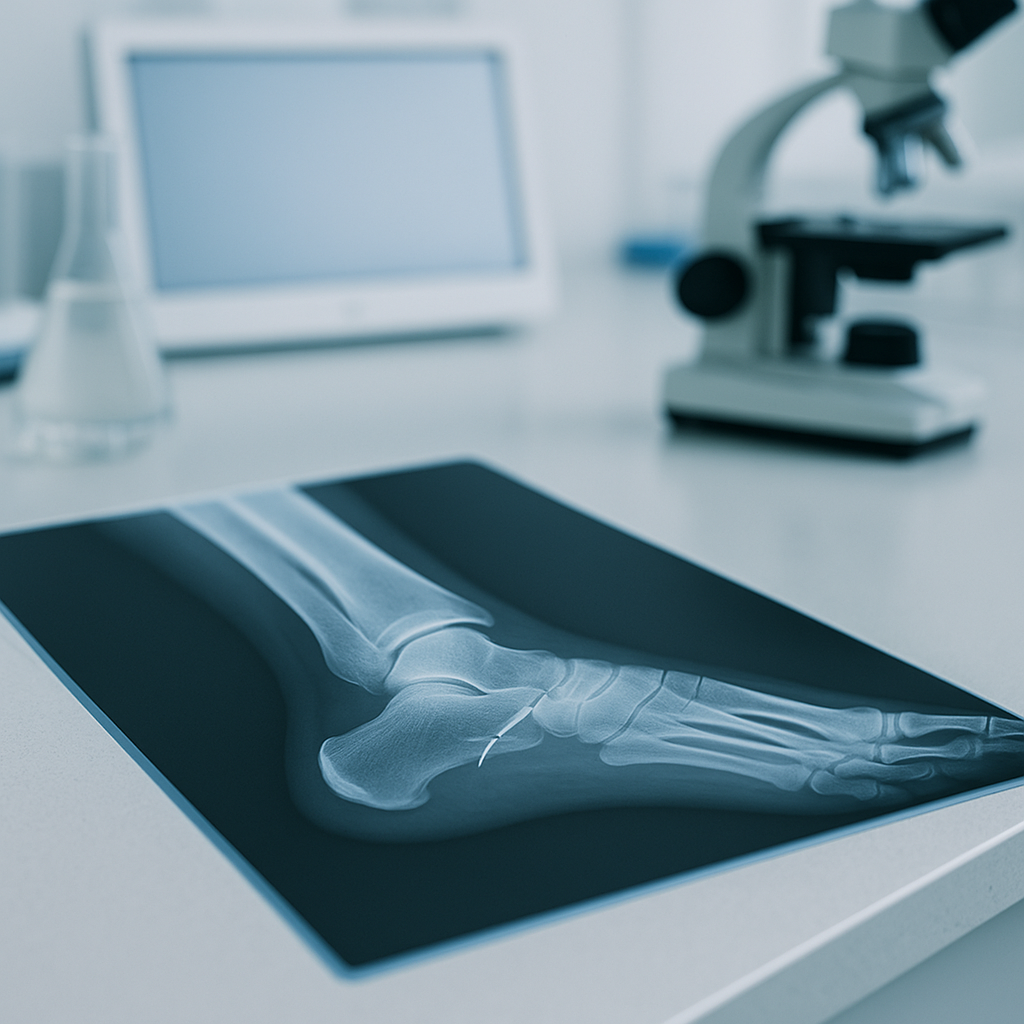

Broken ankles occur when one or more bones of the ankle joint crack or fracture due to impact or twisting. Early diagnosis and stable immobilization support healing, while legal guidance helps preserve evidence and claim value.

Sudden pain, swelling, bruising, deformity, warmth, and inability to bear weight are red flags that need urgent imaging.

Not every ankle fracture looks the same. Doctors classify fractures by bone, pattern, stability, and whether ligaments are torn. Knowing the type guides treatment and informs claim valuation.